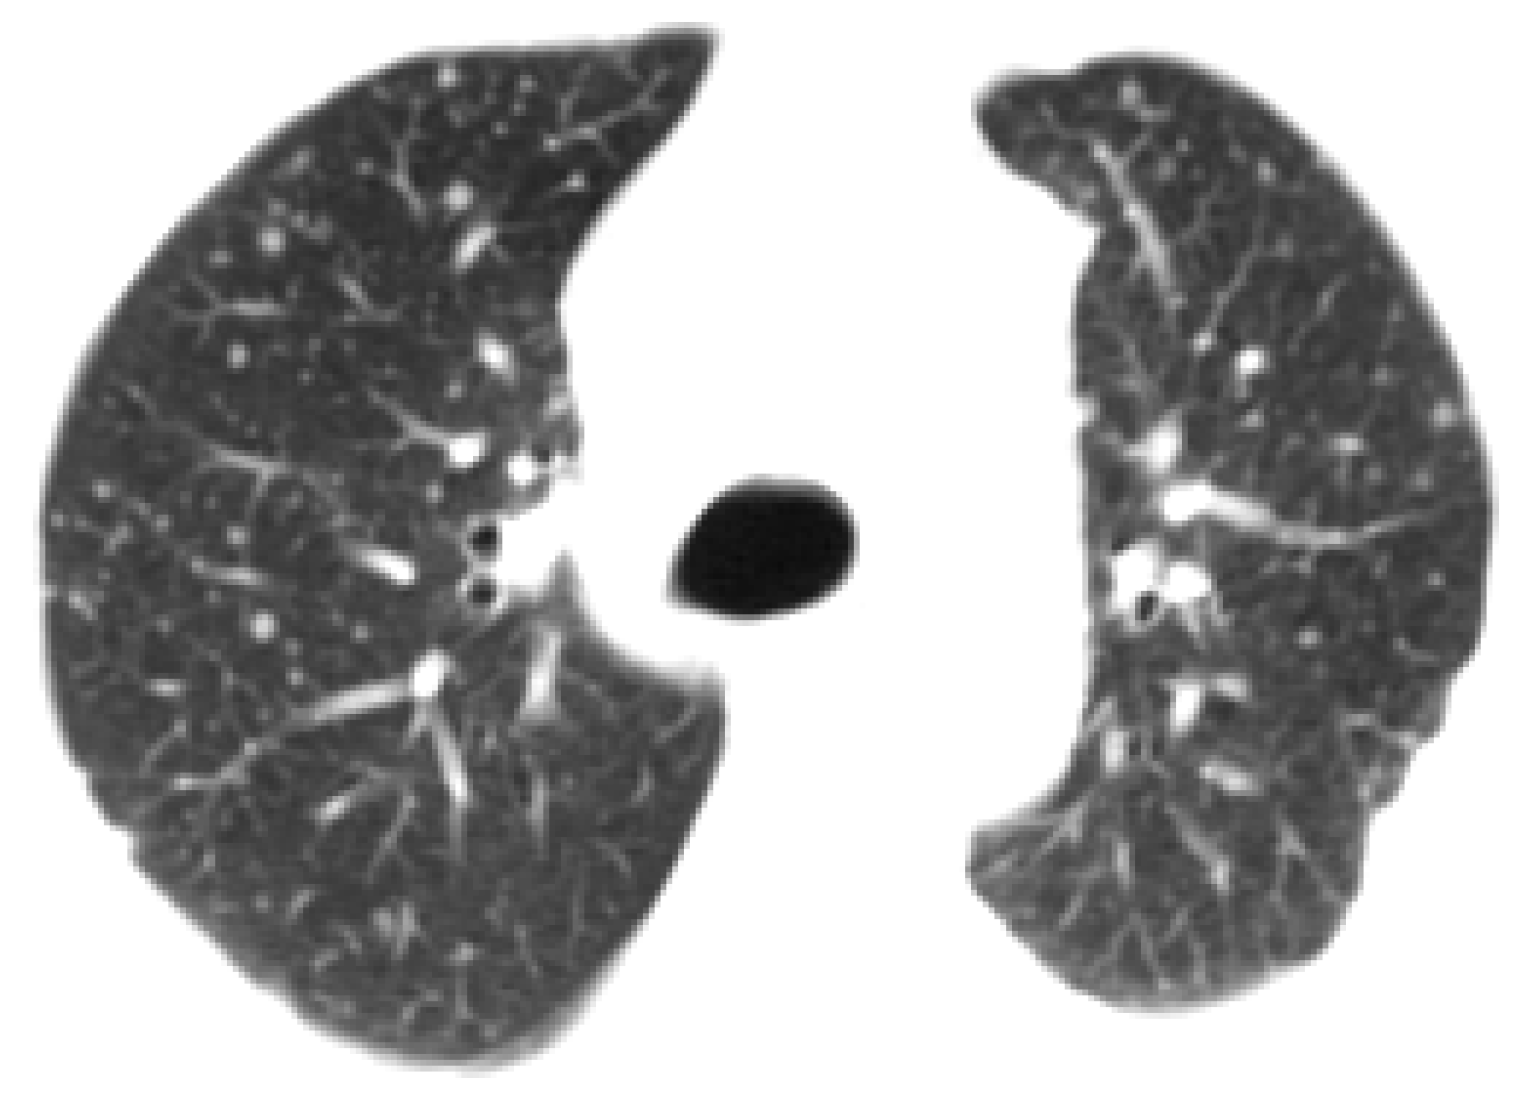

3.3.3. Outlining the Lung Areas with a Box Field

| Algorithm 3: Outlining the lung areas with a box field |

| Input: image I (size of I is width × height) begin x = 0, y = 0, W = 0, H = 0 for i ⃪ 1 to width do for j ⃪ 1 to height if < 0.8 x = i break end end if x 0 break end end for i ⃪ width to 1 do for j ⃪ 1 to height if < 0.8 W = i break end end if W 0 break end end for j ⃪ 1 to height do for i ⃪ 1 to width do if < 0.8 y = j break end end if y 0 break end end for j ⃪ height to 1 do for i ⃪ 1 to width do if < 0.8 H = j break end end if H 0 break end end end Output: image I crop from I, width is W-x, and height is H-y |